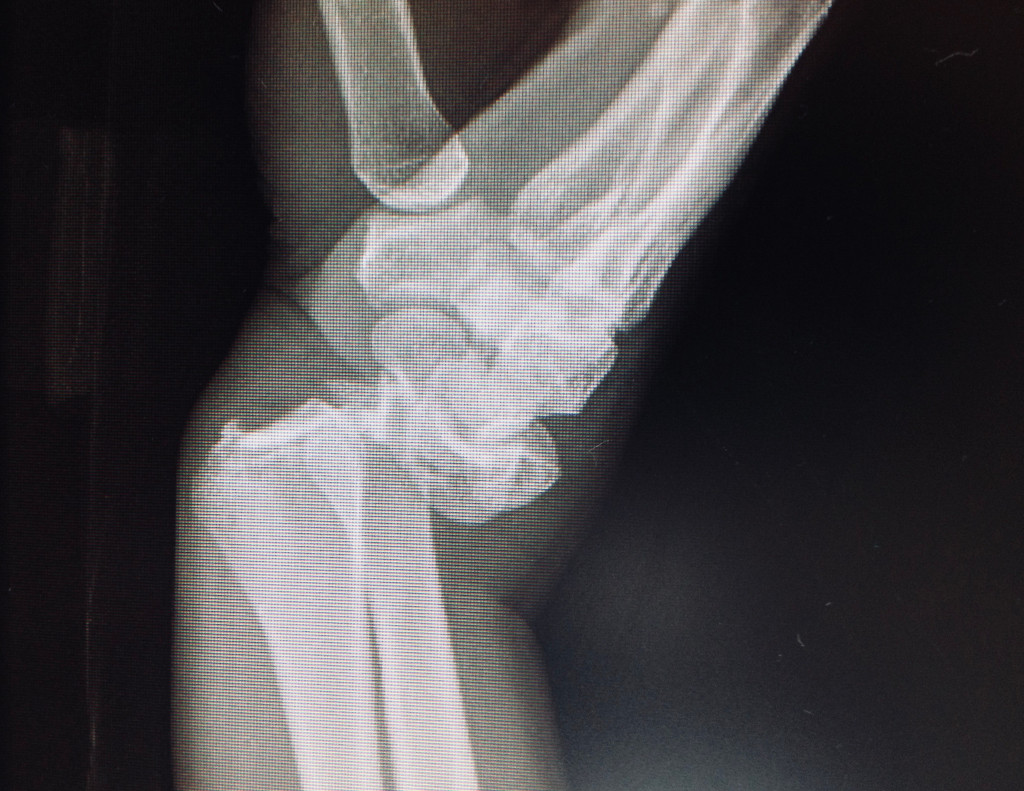

L'examen physique et les radiographies sont essentiels pour le diagnostic précis de ces fractures et pour orienter le traitement. Les radiographies standards peuvent être complétées par un examen scanner si la fracture est intra-articulaire.

- Cas 1 (fractura de radio distal intraticular tratada con placa)

- Cas 2 (fractura conminuta de radio tratada con placa larga)